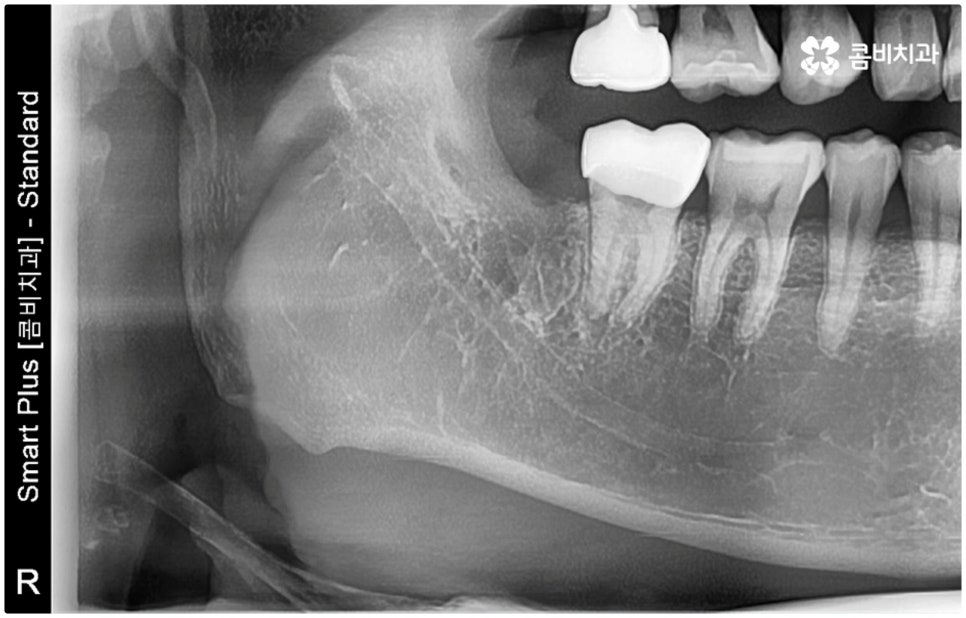

특히 매복 사랑니 중 잇몸 속에 전부 묻혀 있는 사랑니를 완전매복사랑니라고 부르는데 이 경우 누운 방향으로 자라나면서 앞 어금니 뿌리에 지속적인 압박을 가하여 신경을 누르기도 하고 치근을 흡수시키거나 치열이 앞쪽으로 쓰러지게 만들어 부정교합을 유발하기도 하며 드물게는 함치성 낭종이 생겨 턱뼈를 녹이는 상황까지 발생할 수도 있기 때문에 꼼꼼하게 검진을 하여 만약에 필요하다면 늦지 않게 발치 처치를 해 주어야 하는 거예요.

매복사랑니발치치과 를 선택할 때 어떤 것을 기준으로 고르는 것이 좋을까요? 사랑니가 완전히 매복되어 있다면 잇몸을 절개하고 상황에 따라 골삭제 후 치아를 조각내어 빼내줄 필요가 있는데 이러한 과정이 굉장히 까다롭기 때문에 먼저 환자분들의 사랑니 위치 및 뿌리의 형태, 인접 치아 구조, 주변 조직이나 신경 위치 등을 구체적으로 확인할 수 있는 3D CT와 같은 정밀 검진 장비를 갖추고 있는 매복사랑니발치치과 인지 체크해 보실 필요가 있어요.

하악 사랑니의 경우 하치조 신경을 건드리지 않도록 주의해야 하고 상악 사랑니의 경우 상악동 천공을 조심해야 하는데 이 때 환자분들의 상황 또한 개인마다 천차만별인 만큼 각각을 꼼꼼하게 살펴보고 섬세하게 발치 처치를 하기 위해 술자의 뛰어난 기술력 및 숙련도가 요구되므로 매복사랑니발치치과 의료진의 경력 사항을 면밀하게 살펴보시는 것도 도움이 될 거예요.